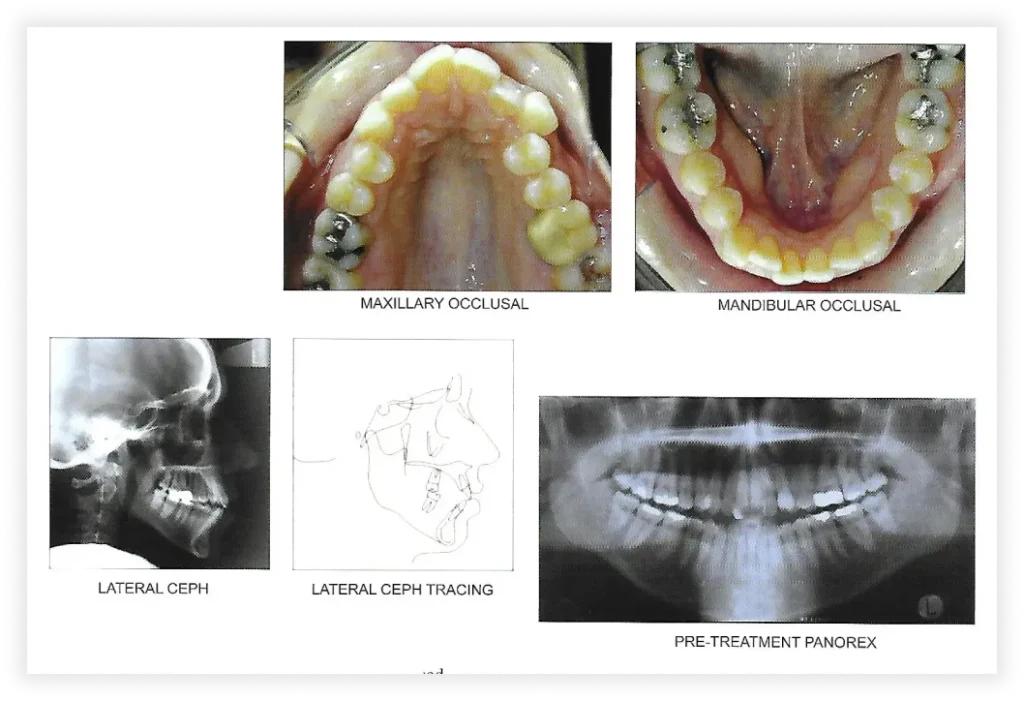

Take a look at some of our cases and successful transformations below.

Case #1

Initial Photos